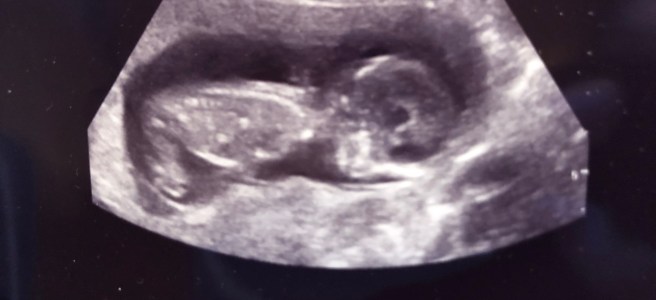

16. januar 2018: Jeg sitter i bilen og griner. Motoren går på tomgang, vindusviskerne visler fram og tilbake over frontruta. Ute laver snøen ned. Jeg skal snart til barnehagen for å være med Rora på PPT-timen hennes. Først skal jeg bare en snartur i butikken. Jeg blir sittende noen minutter. Hikstingen gir seg, tårene stopper. I hånda har jeg to blanke svart/hvitt-bilder. Bildene er kornete, utydelige, men det er ingen tvil om hva de viser: En fullkommen utgave av et lite menneske, 6 cm langt, med hode, kropp, armer, bein – og et lite hjerte. Bildene viser ikke hvordan hjertet slår sine raske slag, heller ikke hvordan den lille kroppen spreller og bølger der den ligger – men det har jeg nettopp sett på skjermen oppe på legekontoret. Lettelsen slår innover meg hver gang jeg gløtter ned på bildene. Først nå innser jeg hvor usikker jeg har vært. Hvor utrygg. Redd for at noe skulle være galt. Men foreløpig står det bra til. Hjertet slår, fosteret vokser slik det skal.